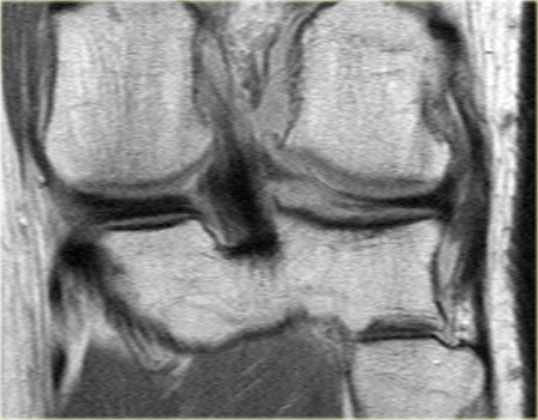

Hãy quan sát hình ảnh bên trái và cố gắng xác định vấn đề của sụn chêm này là gì.

Như bạn đã đoán được qua tiêu đề của đoạn này, đây là một trường hợp sụn chêm lật (flipped meniscus).

Sụn chêm lật là một dạng đặc biệt của rách dạng quai xô (bucket-handle tear).

Sụn chêm lật xảy ra khi mảnh vỡ của sừng sau bị lật ra phía trước, khiến sừng trước của sụn chêm có vẻ to hơn bình thường.

- Thân sụn chêm ngoài.

- Sừng sau quá nhỏ và sừng trước có vẻ to hơn với đường viền không đều.

- Thoạt nhìn có vẻ như có một đường rách dọc ở sừng trước, nhưng thực chất phần sau của cấu trúc này chính là phần lật của sừng sau bị rách.

Cấu trúc phía trước là sừng trước.

Cũng cần lưu ý tình trạng phù tủy xương khu trú và dấu ấn lõm sụn khớp. - Cấu trúc phía trước là sừng trước.

- Một số bất thường ở phần sau.

- Phần sau di chuyển về phía đuôi (caudal).

- Trong hố gian lồi cầu là điểm nối giữa mảnh di lệch và phần còn lại của sừng sau.